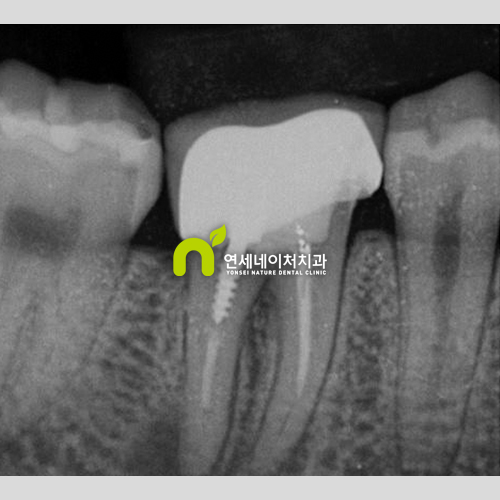

기둥 포스트 심어서 신경치료 한 치아, 염증 재발했다면 발치 해야 하나요?

기둥 포스트 심어서 신경치료 한 치아, 염증 재발했다면 발치 해야 하나요? 안녕하세요. 자연치아를 살리는...